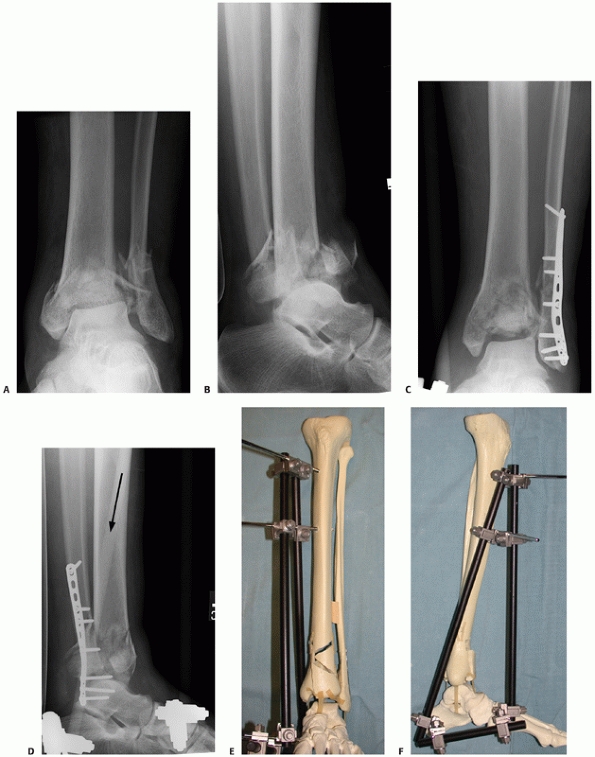

FIGURE 56-8 Anteroposterior (A) and lateral (B)

injury radiographs of a 42-year-old man after falling from a ladder. Initial displacement demonstrates varus angulation with anterior translation of the talus relative to the tibia. The associated transverse fibular fracture at the level of the tibial plafond indicates a tensile failure mechanism of the fibula. After fibular fixation and tibiotalar external fixation, the axial CT scan (C) demonstrates the three commonly identified major fragments: a medial malleolar fragment, an anterolateral (Chaput) fragment, and a posterior malleolar (Volkmann) fragment. Articular comminution is noted between all fracture fragments, most notably at the central intersection of all three fragments. |

Compressive fibular failure is commonly seen with tibial plafond

fractures that present with valgus angulation, whereas tension fibular

failure is commonly identified with tibial plafond fractures that

present with varus angulation (Fig. 56-8). The